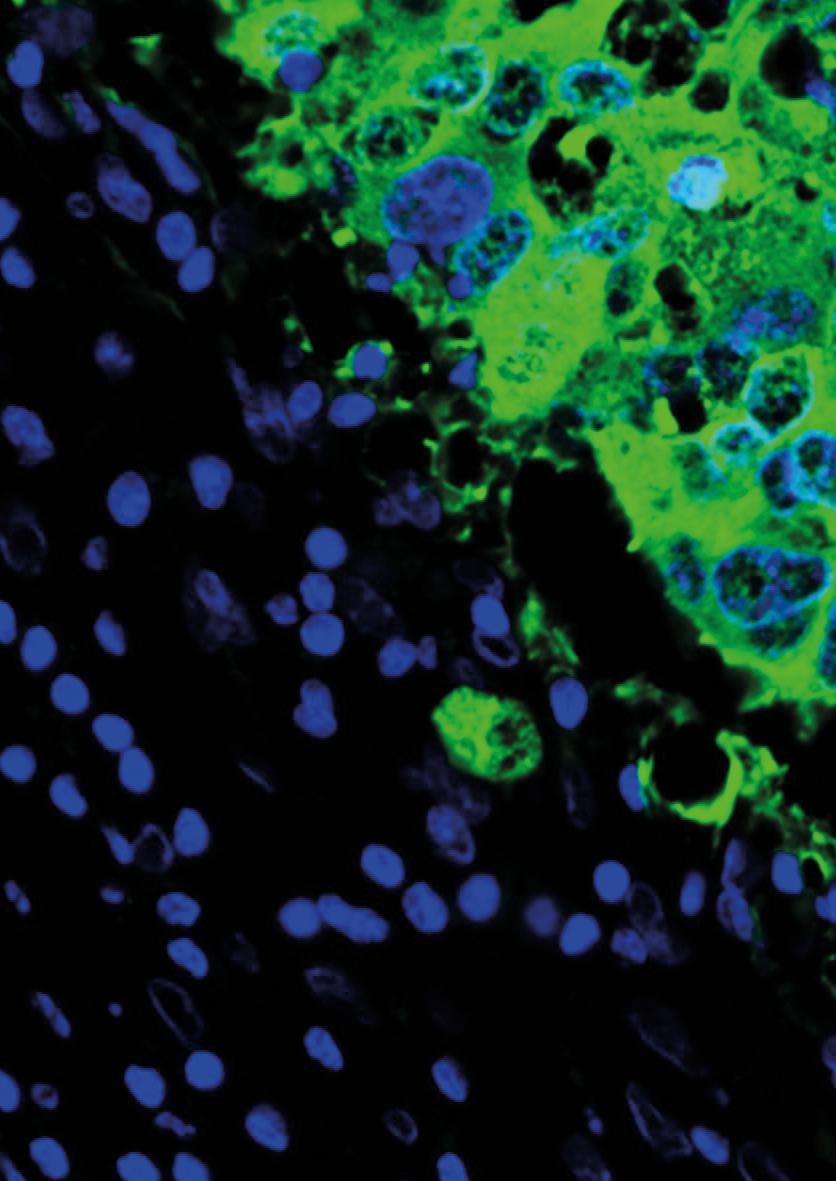

Basal-like breast cancer is an aggressive type of the disease. It often affects younger people and is more common among those from African or South Asian backgrounds – a core part of East London’s population. This type of cancer grows quickly and is hard to treat with traditional methods like chemotherapy.

With the support of Barts Charity funding, Professor Cleo Bishop, based at the Blizard Institute, has been leading a research project along with the Drug Discovery Unit at the University of Dundee, that is developing a new treatment. Called the “one-two punch”, it aims to halt tumour cell growth and can potentially make cancer cells visible to the immune system and easier to attack. This method could be a more targeted and effective treatment with fewer side effects, offering a better prognosis for patients.

“One-two punch” therapy

1. First punch: Stop the growth

Using chemical compounds, tumour cells are forced into a “pro-senescence” state –similar to a sleep-like state in which they can no longer divide or grow. This makes the cancer cells sensitive to the next stage.

2. Second punch: Kill the cancer cells

Once the cancer cells have stopped growing, the second step is to use drugs to kill them. It’s like delivering a knockout punch to the cancer cells after they’ve been immobilised.

The team is now working with the Drug Discovery Unit at the University of Dundee and ValiRx, a drug development company, to advance the new treatment and license it. This could have enormous benefits for patients soon.